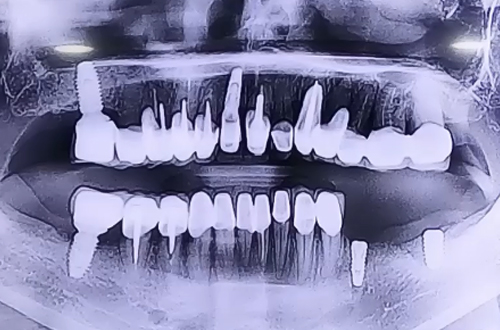

BEFORE

왼쪽 아래 발치한 부분에 임플란트를 이용하여 다시 회복시킬 계획으로 병원에 방문하신 환자분이십니다.

발치되어 있는 부분의 잇몸이 많이 내려가 있는 케이스로 임플란트를 심으면서 눌릴 가능성이 높아 신경 바로 위까지만 임플란트를 심고 나머지 부위들은 주변으로 뼈이식을 병행하여 꼼꼼하게 진행해 드렸습니다.

신경 바로 위쪽으로 임플란트 두 개를 안전하게 심으며 양쪽 임플란트를 브릿지 형태로 왼쪽 아래 보철을 완성 시킬 계획입니다.